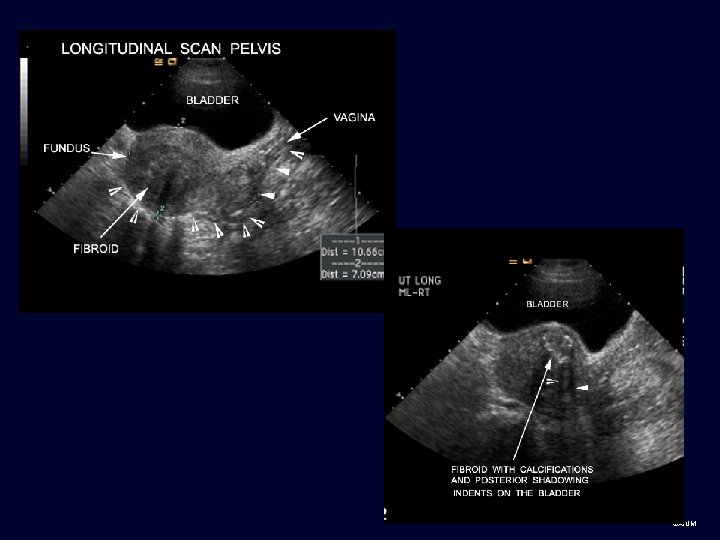

Sound waves • Ultrasound transducer sends sound waves through the body. Sound waves are reflected differently by various types of tissue, and sent back to transducer where signal is transformed into visible image • Sound waves travel through soft tissue or fluid. These types of structures are used as “windows” for US scanning • Sound waves do not travel through and are reflected by air or bone (calcium), resulting in shadowing behind these structures ©AIUM

Technique • Transabdominal sonography uses a distended bladder as window to pelvic structures for a global view. ©AIUM